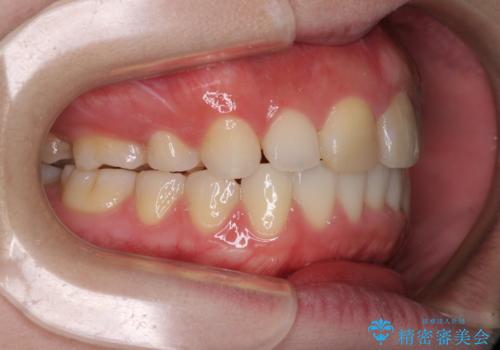

抜歯矯正の後戻り インビザラインによるオープンバイトの再矯正

- 以前矯正治療をされていましたが、後戻りが起きたことを気にして来院された患者様です。

上下前歯のオープンバイトを改善するため、インビザラインにて治療を行うこととしました。

外食が楽しみである患者様だったので、インビザラインによる治療期間は我慢の時期であったようです。

自己管理を徹底していただいたので、1年程度で治療を終えることができました。